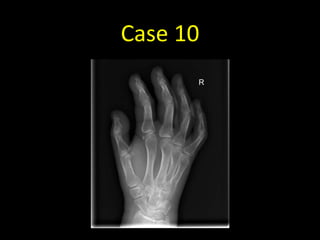

Case 10

• Pain in the right hand after a fall

Case 10 - Image 1

• Fracture of the distal radius

• Always remember to look

at the edge of the film!